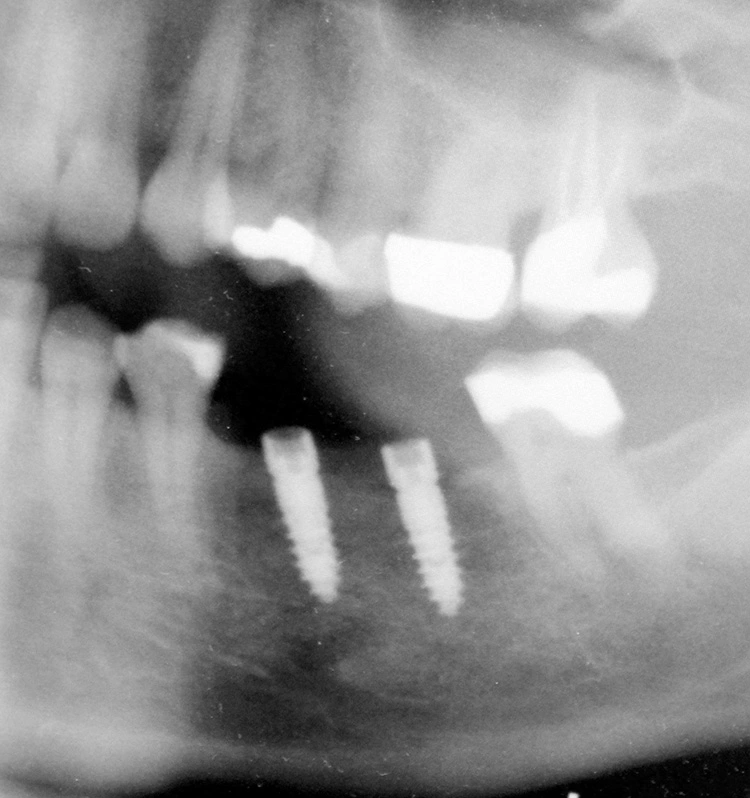

Ein „Geheimnis“ erfolgreicher Implantationen ist, dass die Implantat-Primärstabilität im (harten D1-/D2-) Knochen ausschließlich in der Spongiosa erreicht wird. Ideal ist eine Primärstabilität von 20-40 Ncm, die am besten mit Implantatsystemen erreicht wird, die über einen langen Innenkonus verfügen (z. B. Champions (R)Evolutions, Astra und Ankylos) und ca. 2 mm subkrestal inseriert werden.

Möchte man im D1-/D2-Knochen „Bone-Level“ Kavitäten aufbereiten, so empfehle ich eine „krestale Entlastung“ im kortikal-krestalen (!) Bereich: Für ein ø 3,5 mm Implantat erfolgt dies mit einem ø 4,0 mm Bohrer, bei einem ø 4,0 mm Implantat (für einen Einzel-Molaren) dann auch final mit einem ø 4,5 mm Bohrer. Wir simulieren so eine Sofortimplantation, bei dem die röntgenologischen Ergebnisse auf Jahrzehnte gesehen ebenso wie das „subkrestale Implantieren“ als sehr gut zu bezeichnen sind.